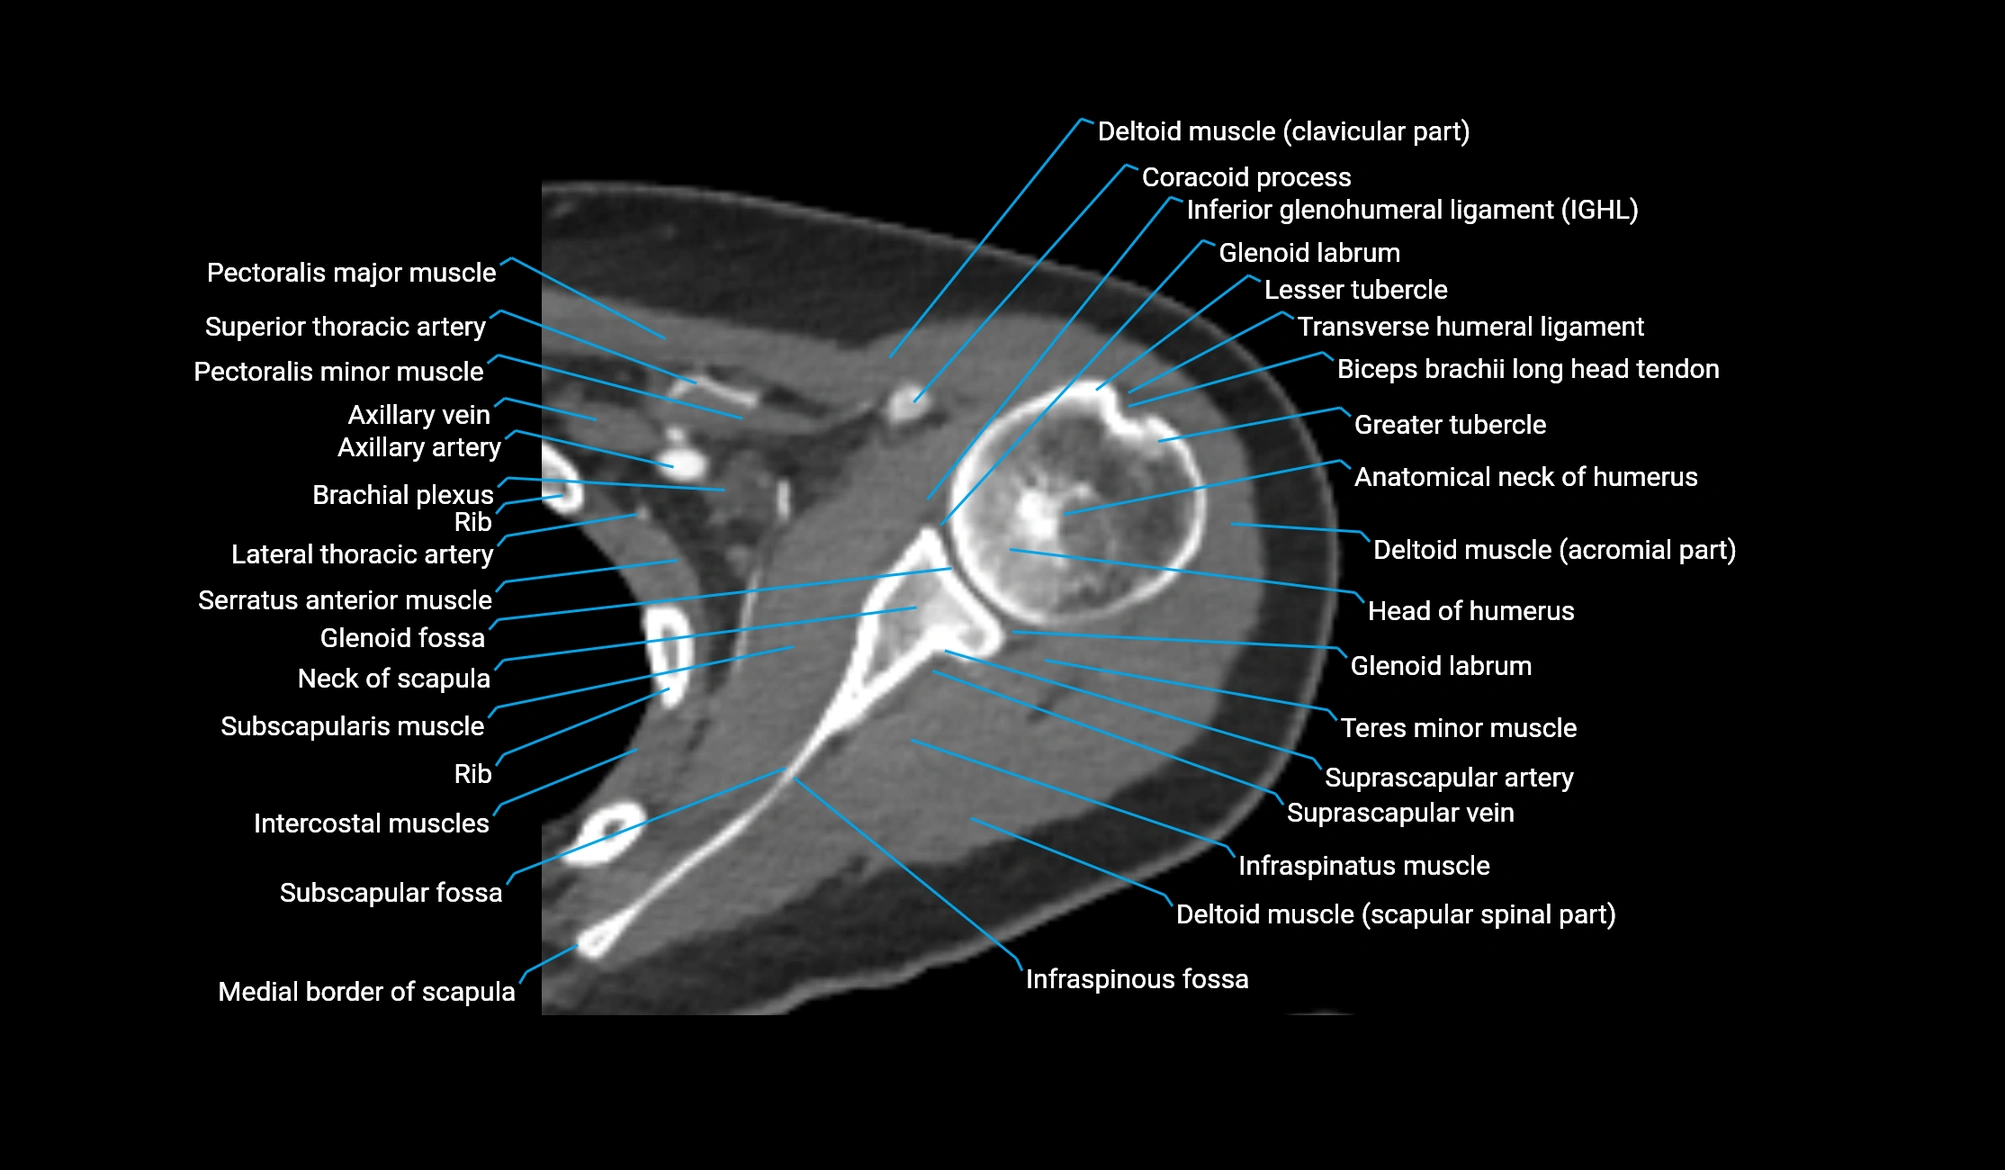

- Anatomical neck of humerus

- Brachial plexus

- Coracoid process of scapula

- Glenoid fossa

- Glenoid labrum

- Head of humerus

- Inferior glenohumeral ligament

- Infraspinatus muscle

- Infraspinous fossa

- Lesser tubercle of humerus

- Long head of biceps tendon

- Medial border of scapula

- Neck of scapula

- Pectoralis major muscle

- Pectoralis minor muscle

- Subscapular fossa

- Subscapularis muscle

- Teres minor muscle